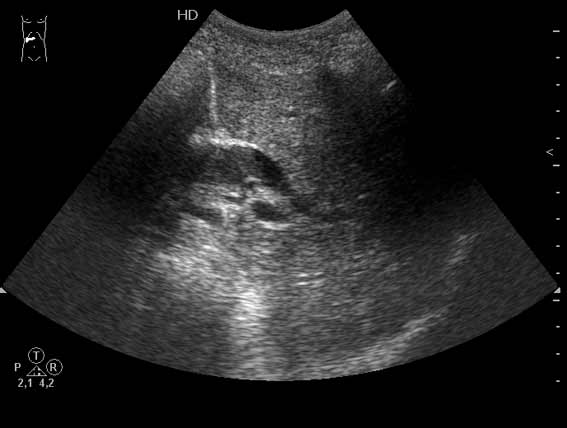

УЗИ холедоха: pus, а не опухоль

Очень пожилая женщина, обратилась в стационар из-за появления желтухи. Периодически беспокоили боли в эпигастрии и правом подреберье.

Желчный пузырь удален по поводу ЖКБ лет двадцать назад.

Дело в том, что в холедохе имеется нечто изоэхогенное (не знаю, видно ли это нечто на ваших мониторах). Врач УЗИ при осмотре перед поступлением в стационар на основании этой картины в заключении отметил возможность опухоли холедоха.

Гнойный холангит на фоне обструкции БДС конкрементом (камень вне скана). В холедохе определяется желчь с осадком, которая может быть ошибочно принята за его опухоль.